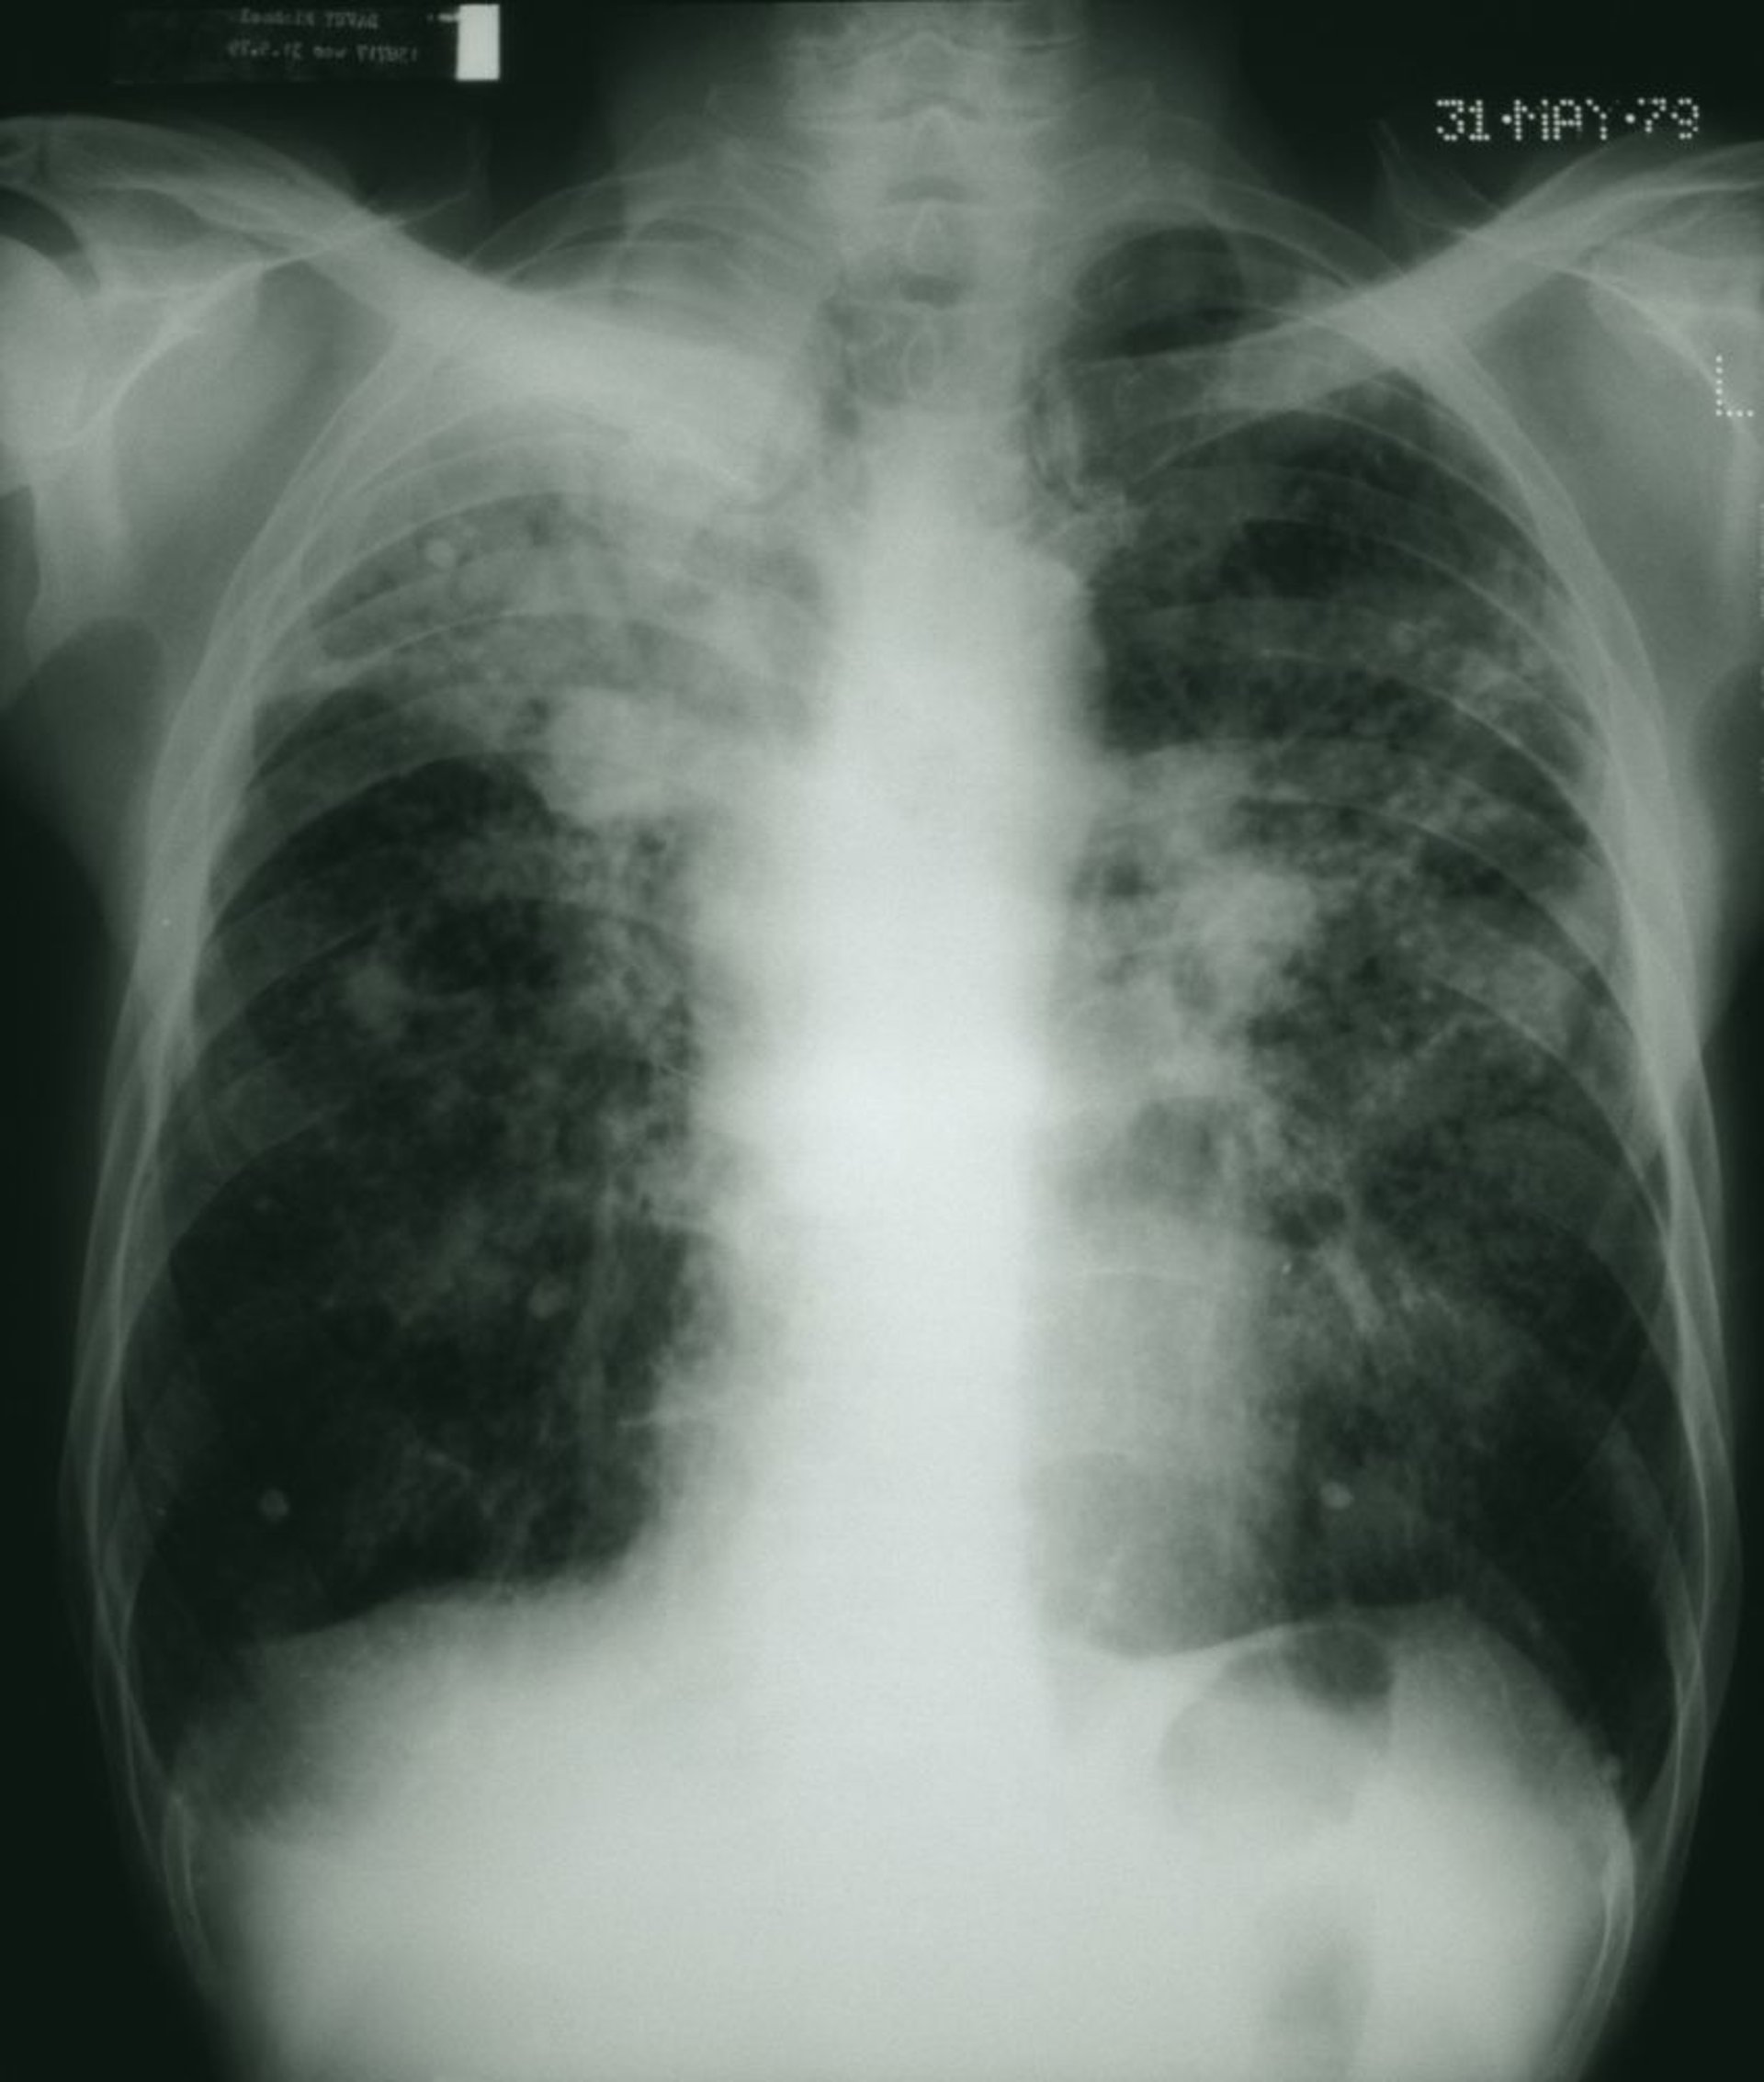

The dark lung fields show a mottled appearance with patches of white fibrous masses consistent with advanced coal worker pneumoconiosis.

STEVE ALLEN/SCIENCE PHOTO LIBRARY